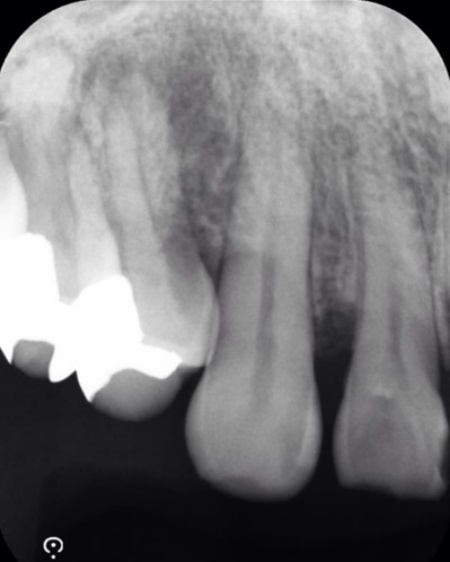

レントゲンを撮影したところ、歯の周囲の骨が溶けて歯ぐきの深い部分にまで歯石が付着していることが確認できました。

半年後のレントゲン検査では、失われていた骨の部分に新しい骨の形成が認められ、歯ぐきの腫れや出血も改善していました。